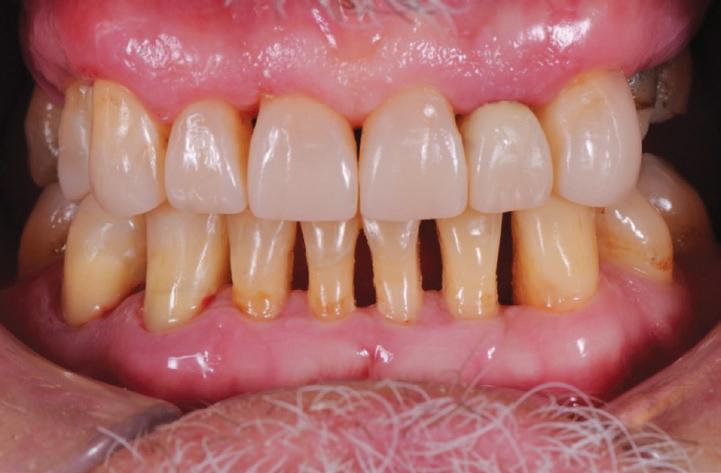

This gentleman presented with pain in his upper left quadrant. He had not been to a Dentist for many years and his dental experience had primarily been to have problematic teeth extracted (Fig. 1). As a result, he no longer had any of his molar teeth, but had been functioning well with his remaining premolar occlusion.

After his examination appointment, it was clear that the two premolars in the upper left quadrant had significant apical pathology and could not be predictably treated. His remaining dentition showed generalised attrition subsequent to dental erosion from gastric reflux, and his lower anteriors showed recession and some loss of periodontal support (Figs. 2, 3).

BEFORE